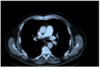

Nedenstående billede er en CT-scanning fra en patient indlagt med akut dyspnø.

Hvad viser scanningen?

- a) Pneumothorax.

- b) Perikardieeksudat.

- c) Bilaterale lungeembolier.

- d) Aorta-dissektion.

- e) Infiltrative forandringer.

(Vælg det mest korrekte svar)

c) Bilaterale lungeembolier.